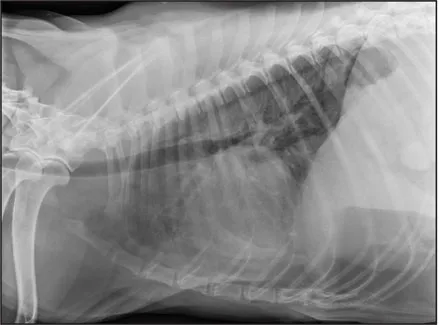

CASE 1.1 A 7-year-old neutered male Labrador Retriever who was hit by a car. You obtain these thoracic radiographs: Figs. 1.1a, b, left and right lateral projections, respectively; Figs. 1.1c, d, ventrodorsal and dorsoventral projections, respectively.

1.1a